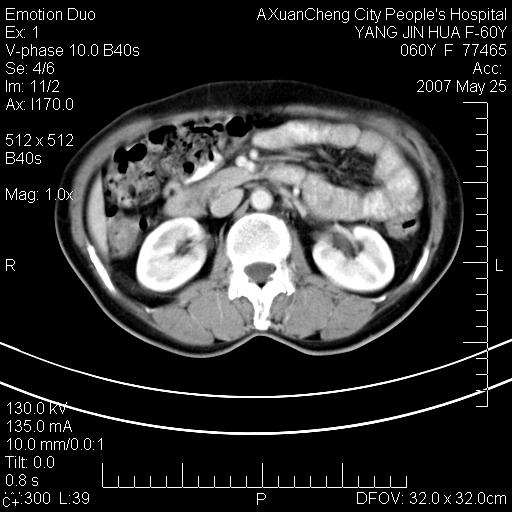

左背部皮下良性肿瘤,密度不均,边界不清,内有脂肪、钙化,增强扫描无明显强化,血管平滑肌脂肪瘤?进一步诊断有困难,建议穿刺活检。

左侧背部皮下混杂密度肿块,结构较疏松,边缘欠光整,内有多发斑点状钙化,考虑:皮下血管瘤。

左背部皮下良性肿瘤,密度不均,边界不清,内有脂肪、钙化,增强扫描无明显强化,血管平滑肌脂肪瘤?进一步诊断有困难,建议穿刺活检。还有,我想还是问一下病史,患者有外伤史吗?能否完全排除外伤后机化的....

其内可见斑点状静脉石,血管瘤有时就不增强化,还是血管瘤。

1、病灶内有小点状钙化,静脉石?这可是血管瘤诊断的重要征象

2、病灶内有脂肪组织增生,血管瘤有此特点

还是考虑皮下血管瘤,强化不明显可能跟大量血栓形成有关,好多战友考虑血管平滑肌脂肪瘤,血管平滑肌脂肪瘤的血管就不强化么?只要有血管就都应该强化。